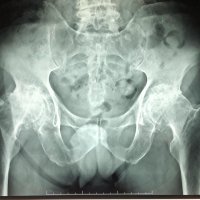

BILATERAL HIP PAIN

M, 77 y.o, with bilateral hip pain.

Anteroposterior pelvis radiograph reveals complete obliteration of bilateral hip joints space with associated marginal osteophyte, subchondral sclerosis and cyst formation, also deformity of femoral heads and acetabulum, in keeping with severe osteoarthritis of the hips.

An asphericity of the femoral heads with osseous “bump” formation at the anterolateral femoral head-neck junction just lateral to the physeal scar is also noted, consistent with cam deformity.

This asphericity leads to unwanted force transmission to the acetabulum during flexion and internal rotation, leading to wear and tear of the labrum dan cartilage, and subsequently resulting in degenerative joint disease.

Cam deformity is usually causes by a primary osseous variant of the head-neck junction, but it also can be the result of several known etiologies include malunion of a femoral neck fracture, slipped capital femoral epiphysis, developmental dysplasia of the hip, or Legg-Calve-Perthes’ disease.